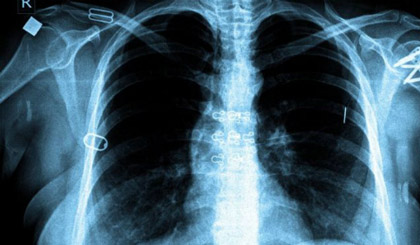

Vốn có thể chữa khỏi, bệnh lao vẫn cướp đi sinh mạng của khoảng 1,1 triệu người vào năm 2014 và trở nên nguy hiểm ngang HIV/AIDS.

Ảnh: BBC.